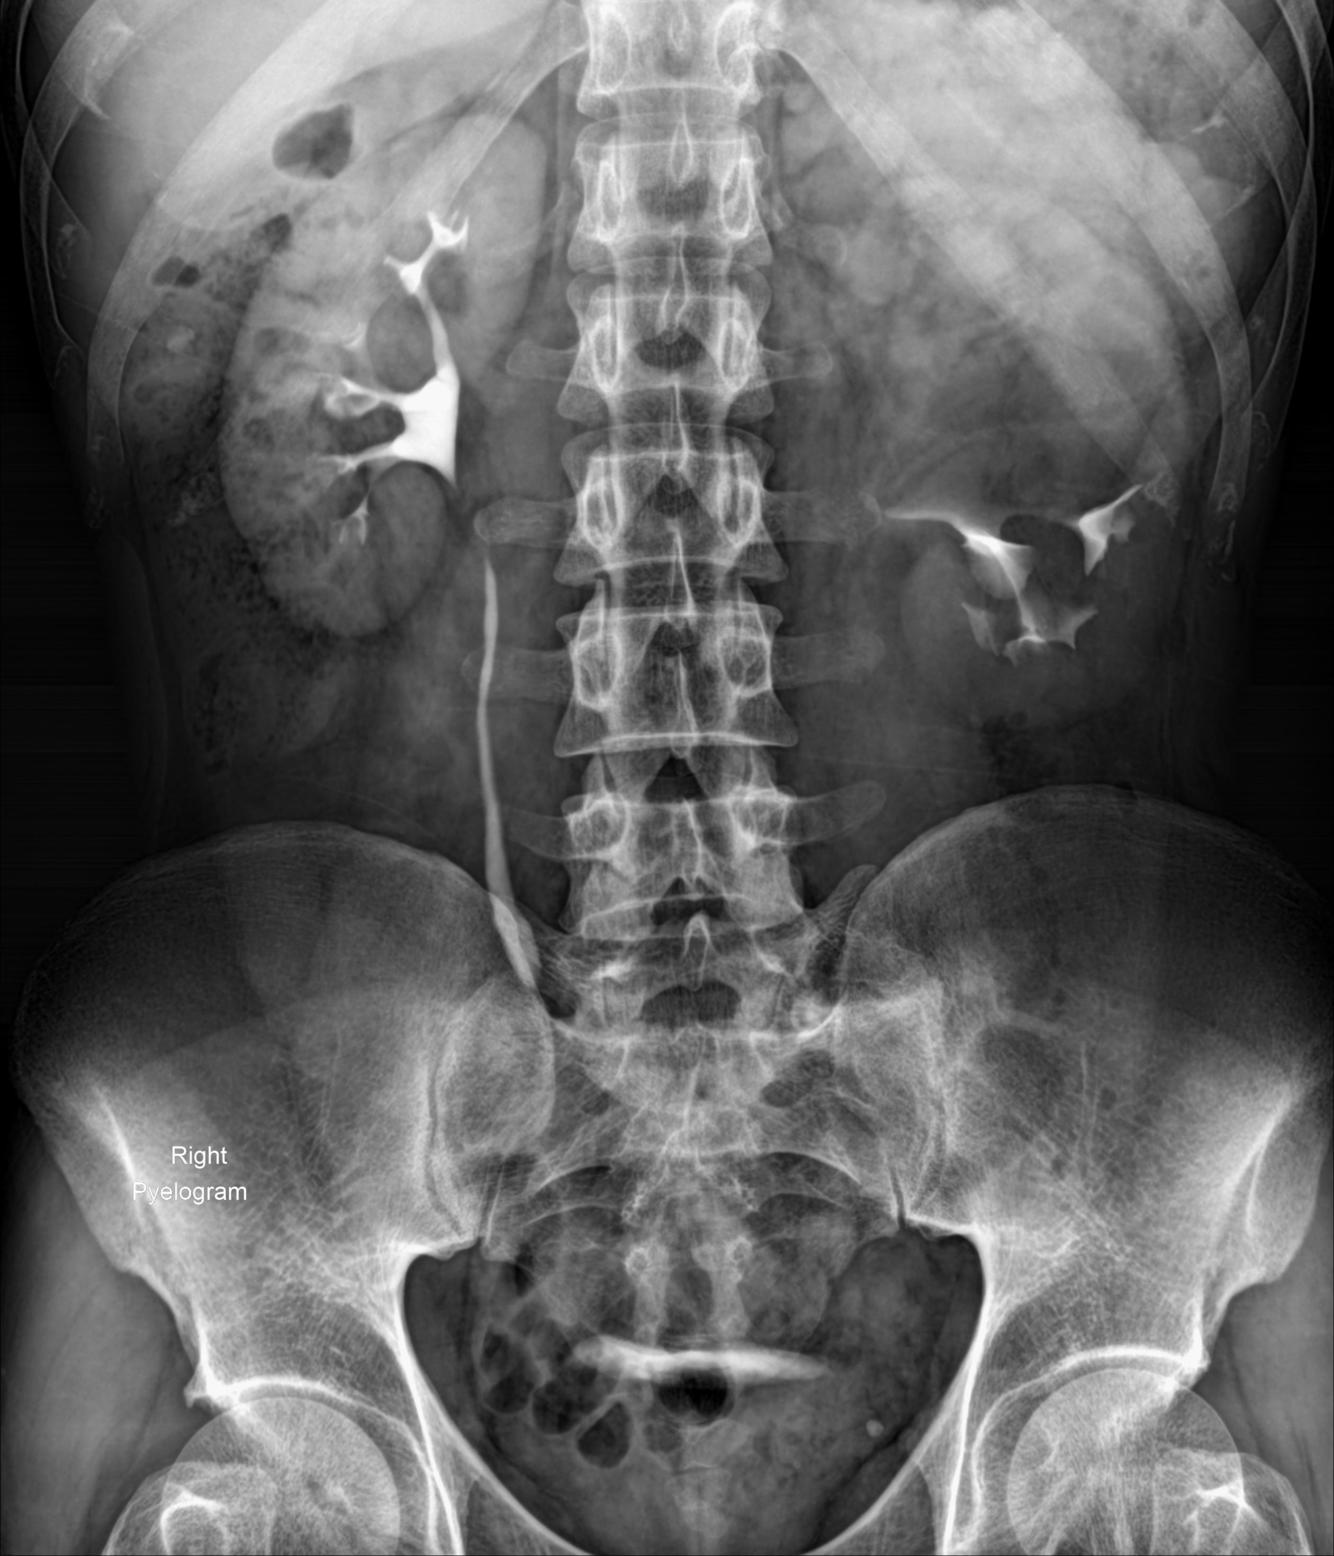

Case Discussion

Left sided duplicated collecting system with the upper moiety obstruction, and non-functioning. It displaces the lower pole moiety inferiorly, mimicking the appearance of a drooping lily.

The drooping lily sign refers to the inferolateral displacement of the opacified lower pole moiety due to an obstructed (and unopacified) upper pole moiety in duplicated collecting system.

Case courtesy of Dr Mohammad Taghi Niknejad, Radiopaedia.org, rID: 54354